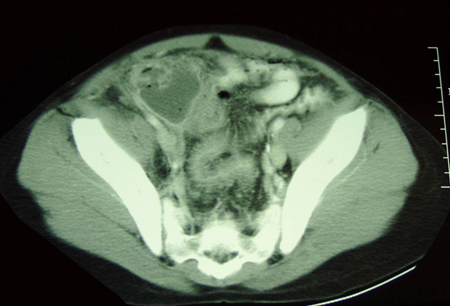

CT scan of a young girl presenting with ovarian torsion. The large pelvic cystic lesion contains calcifications (white arrow) consistent with a teratoma or dermoid cyst

From the collection of Dr KuoJen Tsao; used with permission